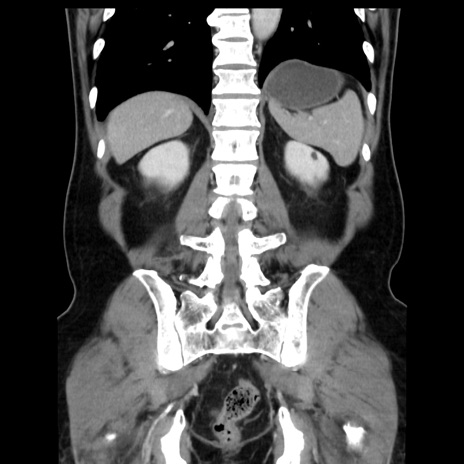

症例16(冠状断像)

【症例】 70歳代男性

【主訴】 腹痛、嘔吐

【現病歴】 約1ヶ月前より間欠的に腹痛と嘔吐あり、当院消化器内科を受診したところCTで多発する肝臓のLDAを指摘され、精査中であった。以降は消化器症状は安定していたが、2日前より嘔気と腹痛があり、同日より排便・排ガスが消失した。改善認めず、 本日、救急外来を受診した。

【既往歴】 大腸ポリープ切除後。

【身体所見】意識清明・会話良好、BT 36.3℃、BP 127/80mmHg、 P 80bpm、腹部:膨満あり、平坦・軟、上腹部正中および下腹部正中に圧痛あり、反跳痛なし、筋性防御なし。

【データ】WBC 7200、CRP 0.77